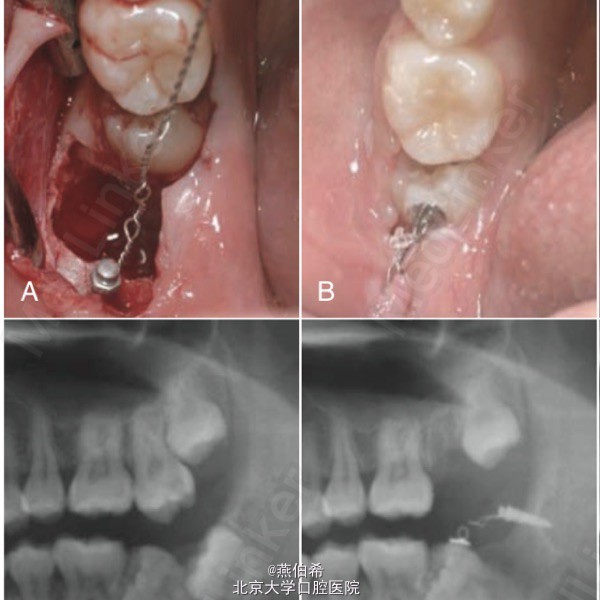

局部正畸,磨牙后垫种植钉直立阻生7

Orthodontics: Current Principals and Techniques (5ed)上病例。美籍韩裔医生完成。下7,8阻生,拔8同时打钉子,直立7